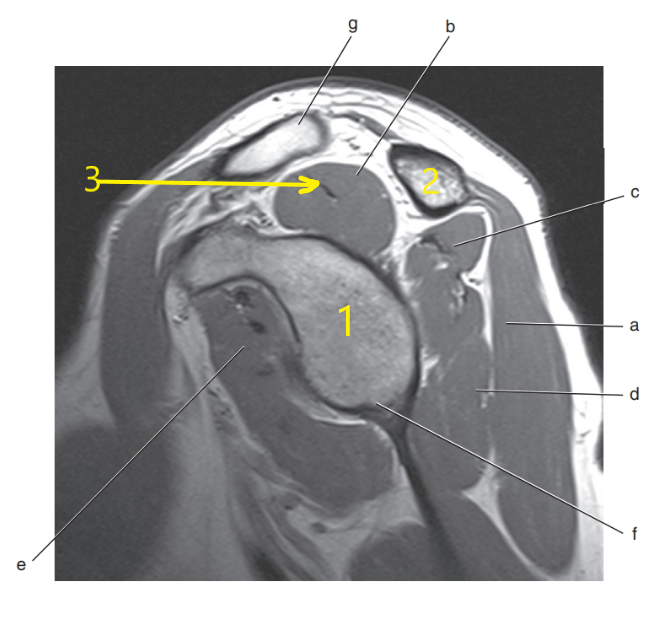

What is # 3 ?

Radius

What anatomy is # 2 ?

Scapula

What anatomy is # 1 ?

Humeral head

What is letter c ?

Superior glenoid labrum

What is letter C pointing to ?

Coracoid process

What is arrow # 3 ?

Teres minor tendon

What is # 2 ?

Acromion Process

What is letter d ?

Acromioclavicular ligament

Subscapularis tendon

What is letter f ?

What is letter b ?

Supraspinatus muscle